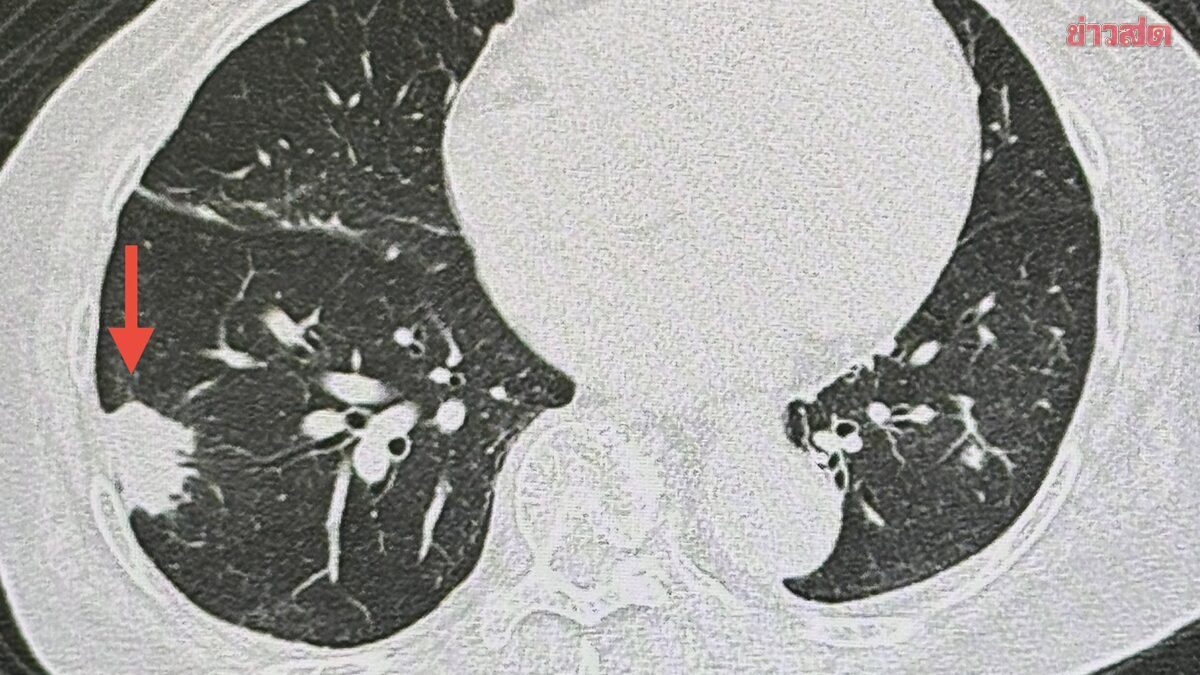

经常清理鸽子粪?小心“真菌”住进你的肺!泰国 84 岁阿婆肺部惊现 3 厘米肿块,罪魁祸首竟然是它 【健康警示 】家人们,快转给家里爱干净的长辈看!清理阳台上的鸽子粪,真的可能致命! 体检发现“不速之客”: 泰国名医 Manoon 医生最近接诊了一位 84 岁的老奶奶。老人家身体一直挺硬朗,不咳嗽也不发烧,结果体检 X 光一照,肺里竟然长了个 3 厘米的大肿块!全家人原本担心是癌症,结果穿刺一看:是隐球菌感染。 阳台上的“隐形杀手”: 老奶奶平时住二楼,楼顶养了好多鸽子。她特别勤快,经常去阳台打扫鸽子留下的粪便。就是在这个过程中,她不小心把粪便里的真菌孢子吸进了肺里,导致了肺部发炎结块。 差点引发脑膜炎: 医生说老奶奶运气好,因为她免疫力还行,真菌只待在肺里。如果这玩意儿跑进血液,钻进大脑,那就是极其危险的“隐球菌性脑膜炎”了! 专家保命建议: 远离鸽群:不要在阳台喂鸽子,更不要让它们落户。 全副武装:如果非要清理鸽子粪,N95 口罩戴好!普通口罩可能挡不住极小的真菌孢子。 湿法清理:建议先喷水打湿再清理,防止孢子随灰尘飘浮被吸入。 网友热评: “天呐,我妈每天都在阳台刷鸽子屎,看完赶紧转发家庭群!” “之前听说过这种病,真的很折磨人,千万不能掉以轻心。” “鸽子虽可爱,粪便全是毒,大家引以为戒吧。” #隐球菌性肺炎# #鸽子粪的危害# #泰国医生提醒# #呼吸道健康# #生活健康小常识# #千万别吸入鸽子粪孢子#